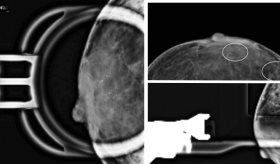

Por esta razón, el Instituto Nacional de Salud y el Departamento de Oncología han impulsado estudios comparativos sobre la efectividad de radiografías y tomografías computarizadas (CT scan) en la detección temprana. Los resultados han demostrado que, en grupos de riesgo, el uso de CT scan permite identificar el cáncer en etapas iniciales, aumentando las oportunidades de tratamiento y curación.

El pulmonólogo explicó que el seguimiento con radiografías de tórax no es la opción más adecuada para detectar cáncer de pulmón en pacientes de alto riesgo. En su lugar, recomienda la tomografía computarizada (CT scan) de baja dosis, especialmente en personas con más de 20 años fumando una caja de cigarrillos al día o en exfumadores que dejaron el hábito hace menos de 15 años. Este método ha demostrado ser eficaz en la detección temprana de la enfermedad, lo que aumenta las posibilidades de un tratamiento exitoso.

En Puerto Rico, existen varios centros que realizan tomografías computarizadas de baja dosis para la detección temprana del cáncer de pulmón. Sin embargo, en pacientes con antecedentes de exposición significativa y síntomas como tos persistente, hemoptisis o dificultad para respirar, así como en aquellos con enfermedades respiratorias crónicas, podría ser más adecuado realizar una tomografía convencional. Aunque este método implica una mayor exposición a la radiación, permite identificar hallazgos específicos que pueden ser clave para el diagnóstico.